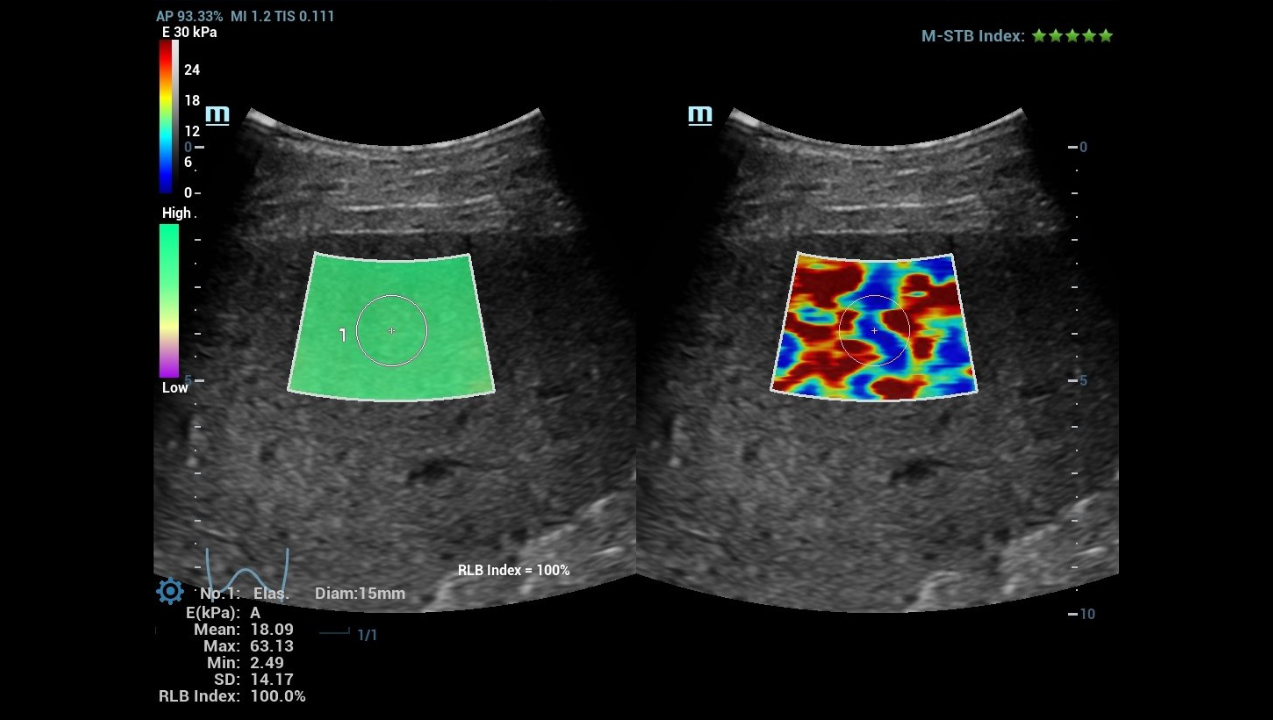

High Frame Rate Sound Touch Elastography (HiFR STE)

hifr-ceus-liver-fig4-pc

Sound Touch Quantification (STQ)